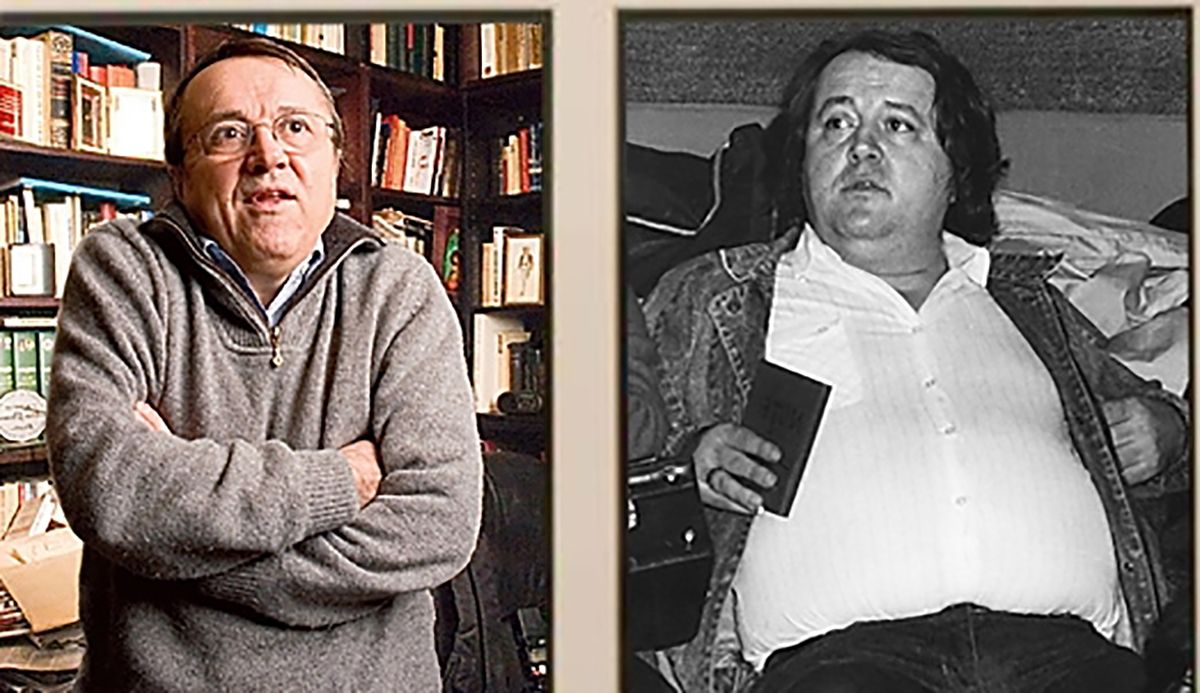

Postarea a fost însoțită și de imagini pentru a arăta cum se poate schimba conformația corpului, dar și cum arată un chist în organism.